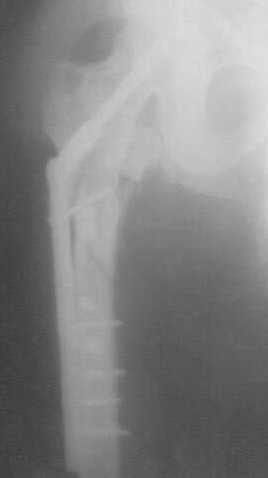

Глубокоуважаемые коллеги! Благодарю за полезные советы, которые нам очень помогли в выборе оперативной тактики пациента. 13.02.08 мы выполнили первый этап оперативного лечения этого больного. Вначале зафиксировали левое бедро АВФ Гофмана

(главный травматолог области достал из каких-то «анналов», первый раз в жизни увидел этот аппарат в живую). После наложения «ДРУ Челнокова» выполнили ЗИО правого бедра реконструктивным штифтом Chm. Далее уложили пациента на левый бок и выполнили остеосинтез вертлужной впадины. Ограничились задне-латеральным доступом без отсечения вертела, чтобы не утяжелять операцию. Результат прилагается.

Следующим этапом планируем выполнить ЗИО левого бедра.